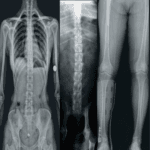

El software costura (Stitching en inglés) es utilizado para tomar imágenes panorámicas de

columna y extremidades en el ámbito ortopédico.

Tiene como objetivo principal la creación de imágenes de alta calidad mediante la

combinación (o “costura”) de múltiples imágenes tomadas desde diferentes ángulos o

posiciones.

Es particularmente útil en áreas como la columna vertebral, las extremidades y otras zonas

donde las estructuras son demasiado grandes para ser capturadas en una sola toma con un

solo ángulo o exposición.